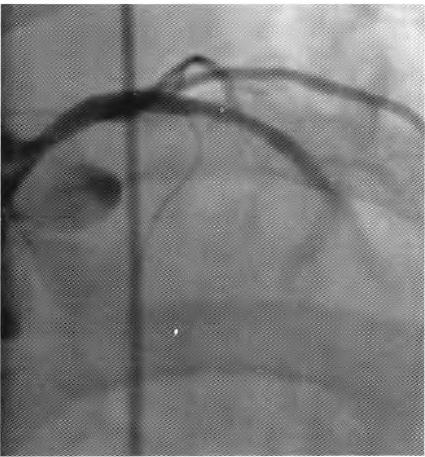

患者择期于10月25日行冠状动脉介入治疗,术前常规给予地塞米松10 mg静脉注射,右侧桡动脉穿刺成功后,经鞘管送多功能造影导管至主动脉窦部,对比剂选择碘帕醇(商品名:碘必乐),导管“吾烟”后数秒钟,患者血压骤然降低至50/30 mmHg,心率逐步增快至90次/min左右,予羟乙基淀粉130/0.4氯化钠注射液(万汶)加压快速静脉滴注100 mL,反复3次静脉注射多巴胺3 mg,血压65/40 mmHg左右,约3 min后心率降至40次/min左右,监护示室性逸搏心律,继之心跳、呼吸骤停。持续胸外按压,气管插管机械通气,持续静脉泵入肾上腺素0.2仙g/(kg•min),并间断4次静脉注射肾上腺素0.5 mg,血压维持在105/50 mmHg左右,进一步行左室造影,见图1。以及左冠状动脉造影,见图2。氧饱和度降至75%,考虑对比剂致高敏反应,引起过敏性休克,静脉滴注甲泼尼龙500mg,经右侧股动脉路径行主动脉内球囊反搏术(intra.aortic balloon pump,IABP)治疗,同时联系外科、麻醉科、体外循环科经左侧股动脉一股静脉行体外膜肺氧合(extra—corporeal membrane oxygenation,EC—MO)支持治疗。ECMO置人后将患者由导管室转送至冠心病监护病房(coronary care unit,CCU)继续抢救治疗,床边心脏超声,见图3。提示室间隔水肿(厚度1.53 cm)。在置人ECMO初期维持绝对镇静,下调直至停用血管活*药性**物,心律以室性逸搏心律为主(持续约48 h),偶然有室速、室颤发作,未作处理。在置人ECMO第3天因急性肾衰竭行床旁连续静脉静脉血液滤过(continuous veno—venous hemofiltration,CVVH)治疗,第4天后患者心率、血压稳定,复查心脏超声提示左心室射血分数40%,撤除ECMO,此后依次拔除气管插管、撤除IABP以及停止CVVH等治疗,患者恢复良好,于11月14日出院。

图2左冠状动脉造影未见冠脉损伤或冠脉急性血栓事件.冠状动脉前向血流瘀滞

在冠状动脉介入诊疗术中发生心脏骤停,针对尚处于心肌梗死(尤其是急性ST段抬高型心肌梗死)急性期的病例,要首先考虑心肌梗死后机械并发症(如心室游离壁破裂、室间隔穿孔等)、冠脉急性血栓栓塞事件以及医源性冠脉损伤等,并迅速行相关检查措施排查,如能排除以上危重情况,则要考虑对比剂导致过敏性休克。该患者术中左室造影排除心室游离壁破裂,左冠状动脉造影排除左主干或左冠血管急性血栓栓塞事件以及医源性冠脉损伤,再结合患者存在药物(多种抗生素)过敏史,因此,诊断对比剂致过敏性休克明确。后期心脏超声提示“心肌水肿”,亦是器官组织对过敏的一种表现。